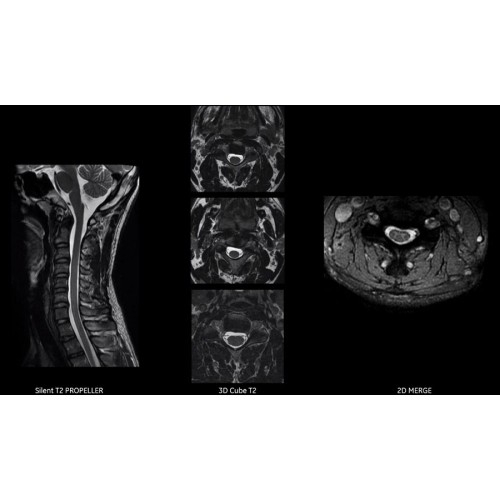

Система SIGNA Pioneer воплощает поразительные достижения в области визуализации. Передовая технология Total Digital Imaging (TDI) позволяет добиться большей четкости изображений и на четверть повысить соотношение сигнал/шум.

• Технология Digital Surround Technology (DST) — это новая технология объемной оцифровки данных, объединяющая сигналы от каждого элемента катушки. Прекрасное соотношение сигнал/шум и чувствительность поверхностных катушек в сочетании с превосходной однородностью и высокой проникающей способностью встроенной радиочастотной катушки — все это позволяет создавать качественные изображения не только позвоночника, но и всего тела.

Благодаря революционному программному пакету Silent Suite уровень шума снижается до 77 дБ, что всего на 3 дБ выше уровня окружающей среды. Программный пакет Silent Suite теперь включает полный пакет приложений для исследования ЦНС (T1, T2 FLAIR, DWI10, МРА). Кроме того, мы расширили возможности визуализации Silent за пределы ЦНС для исследований скелетно-мышечной системы и позвоночника. Silent Suite – платформа, содержащая в себе все импульсные последовательности для бесшумного сканирования.